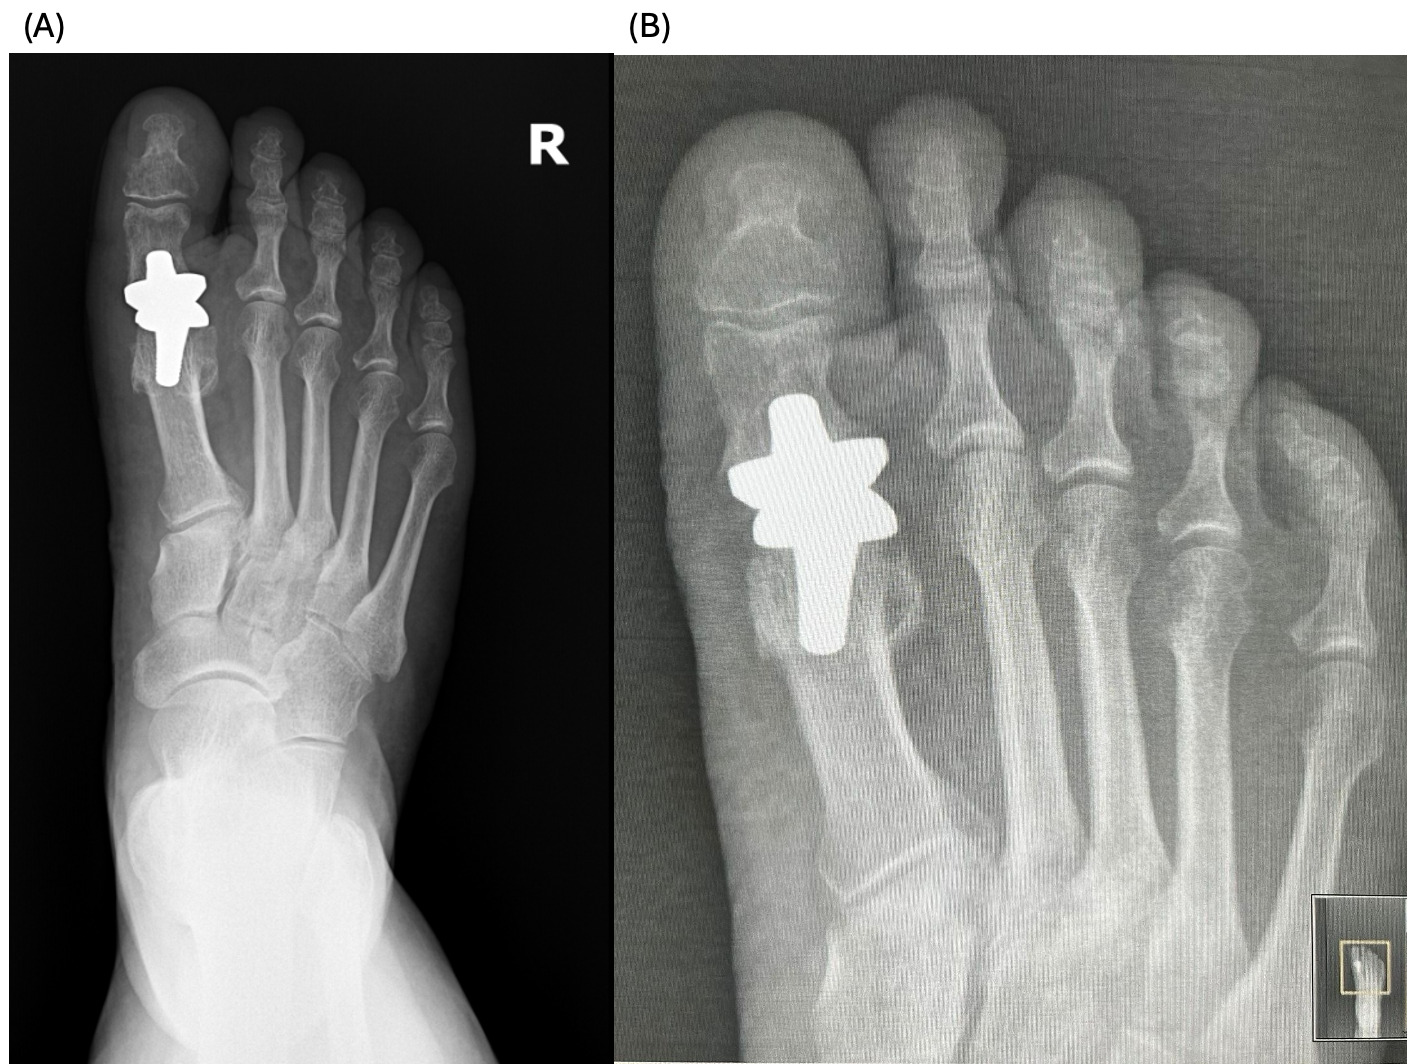

A 63-year-old female patient with a limited range of movement in her right leg, pain during walking or using stairs for the last 1 year, reports significant worsening of the pain after stepping incorrectly 2 weeks ago, with a temporary effect of NSAIDs. Physical movement revealed the movement for 10-15 degrees in the 1st MTP joint, accompanied by pain (Figure 2, A).

2 and 6 months after surgery, the patient reports mostly preserved mobility of the joint, absence of pain (Figure 2 B, C). In addition, the patient reports improvement of edema and a decrease in weight.

The patients had undergone radiographic evaluation of the MTP joint before the surgery, right after surgery, and 2 and 6 months after surgery (Figures 4-9). The radiographic imaging after the surgery confirmed the correct positioning and alignment. At the follow-up, the radiographic images were done to analyze the early healing process, to observe if there were any signs of implant loosening. 2 months after the surgery, no patient had periprosthetic radiolucencies, no stress-related changes. 6 months after surgery, no osteolysis, no migration of the implant.

This case series demonstrates successful short-term results following total first metatarsophalangeal (MTP) joint replacement using ceramic implants in patients with hallux rigidus. All three patients presented significant improvement in AOFAS scores within 2 months postoperatively, with preserved improvement at 6 months. Notably, Patient C, who had the lowest preoperative score (27/100), achieved the greatest relative improvement, reaching 92/100 at 2 months and 89/100 at 6 months. These functional outcomes were confirmed by physical examination findings, with clear improvements in joint alignment and reduction in deformity (Figure 1-3, (B, C)). Moreover, radiographic imaging revealed no signs of complications such as implant loosening, migration or stress-related changes.